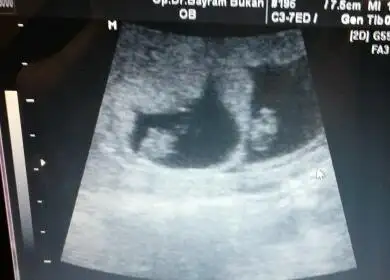

Kizlar benim simdi bebek daha buyuk ama bu ilk ultrasyondaki görüntü karindan tahminleriniz nedir acaba

aaaa sevindim.canim gozunuz aydin benim ikizler 8+2 usg paylastim sen ne diyorsun canimcanım kıza benzettim ben bunu hem kese hem konum olarak. bi önceki ultrason varsa ona bakiyim daha küçükken. bu arada ablamında bebiş gözüktü çok şükür :) ama onunki tek çıktı ikiz değilmiş.

8+0 canim baskada varmi bilmiyorumcanım kıza benzettim ben bunu hem kese hem konum olarak. bi önceki ultrason varsa ona bakiyim daha küçükken. bu arada ablamında bebiş gözüktü çok şükür :) ama onunki tek çıktı ikiz değilmiş.

eğer karındansa erkek canım ikiside :) rabbim gönlüne göre versin.aaaa sevindim.canim gozunuz aydin benim ikizler 8+2 usg paylastim sen ne diyorsun canim

Canim kiza benzettim ben hem kese hem bebegin konumu kiza benziyor. Tabi bizimki sadece bi tahmin.Eki Görüntüle 1807457 Eki Görüntüle 1807458 burda 8 hafta 3 cü günümüz dü